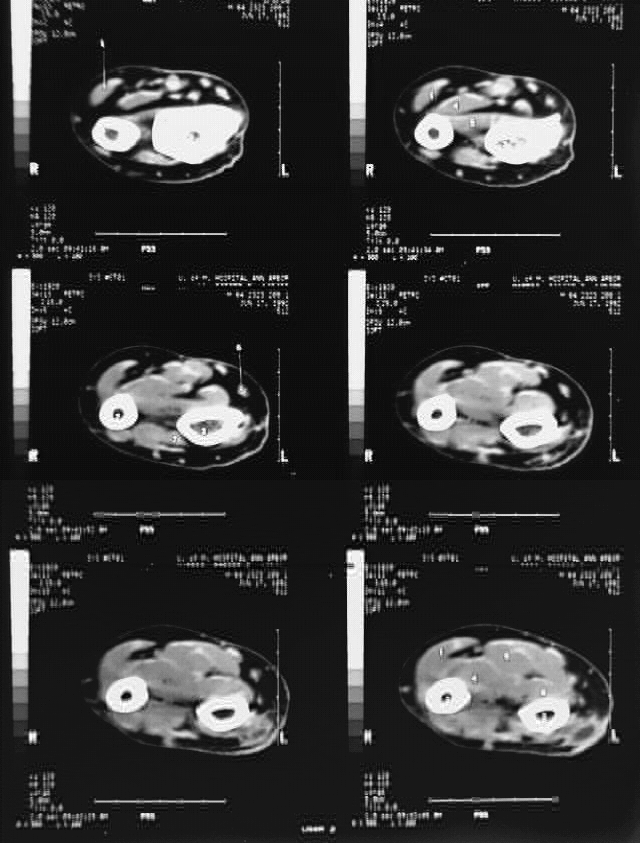

Radiology Images

Upper Limbs: Arm CT Film 9: